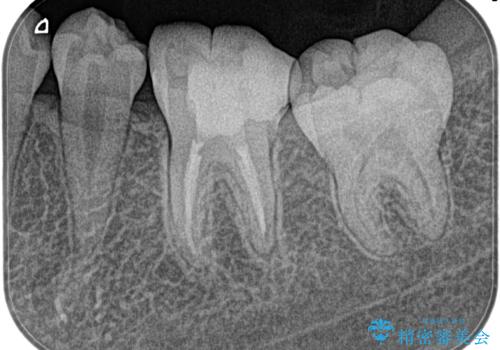

昨晩から激痛。精密根管治療

- 奥歯がズキズキ痛いことを主訴に来院されました。

検査の結果、診断を症候性不可逆性歯髄炎、症候性根尖性歯周炎とし抜髄を行っております。

根管充填はCWCT。

根管形成はマルテンサイト相を有するNi-TIロータリーファイル(NEX MS) 使用。